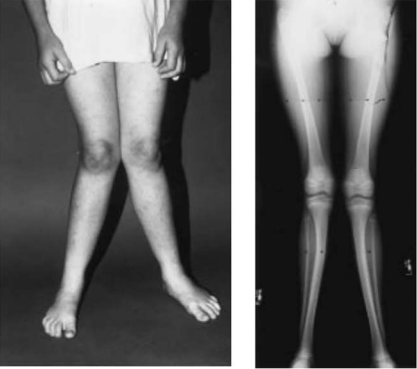

Children with neuromuscular disorders may develop knee valgus. Ambulatory children with cerebral palsy and other neuromuscular diseases often have foot valgus and/or excessive tibial torsion, causing the foot to rotate outside the knee (Figure 5). Due to this defect, there is valgus and external rotation of the knee in ground reaction while standing. These abnormalities, along with growth and weight gain, can lead to the development of valgus deformity in the foot, ankle and knee joints. It is thought to be caused by iliotibial band contracture20 and the effect of abnormal deviation (valgus thrust) with Trendelenburg walking or other walking support.

Fig. 5 Ambulatory 11-year-old child with neuromuscular disorder. External rotation of the foot is due to pes valgus and external tibial torsion. As a consequence, the ground reaction force passes lateral to the normal weight-bearing line, potentiating deformity in the foot and ankle and creating a valgus moment at the knee, which in time can lead to progressive deformity there as well.